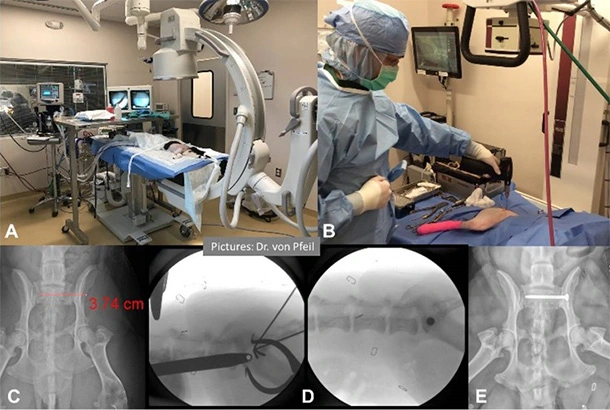

Luxation des Beckengelenkes

Luxation des Beckengelenkes (Sacroiliac – Luxation; ISG; Kreuzbein)

Wird typischerweise behandelt via minimal invasiver, fluoroskopisch geleiteter Operation.

Meist traumatisch verursacht, kann diese schwerwiegende Verletzung mittels minimal invasiver Chiurgie optimal versorgt werden.

A: Patient, vorbereitet für die Behandlung unter fluoroskopischer oder radiologischer Führung (B). C: Röntgenbild und Planung vor der Operation. D: Intraoperative Ansichten. E: Nach der Operation. Die Platzierung der Schraube erfolgte durch einen 1.5 cm langen Hautschnitt. Der Patient war am folgenden Tag lahmheitsfrei.